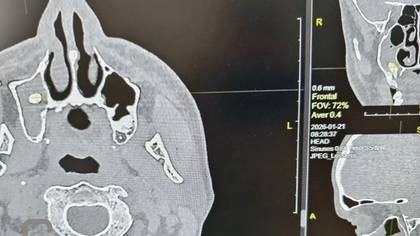

Доктора Орской городской больницы провели уникальную операцию, вернув пациенту способность полноценно дышать. Мужчина обратился в хирургический стационар с жалобами на одышку, однако обследование выявило крайне редкое осложнение: после посещения стоматолога один из зубов «мигрировал» в носовую пазуху.

По словам специалистов медучреждения, на первичной стоматологической процедуре произошла перфорация костной перегородки, разделяющей альвеолярный отросток и гайморову пазуху. Зуб сместился в непривычную анатомическую полость, где застрял, спровоцировав закупорку дыхательных путей.